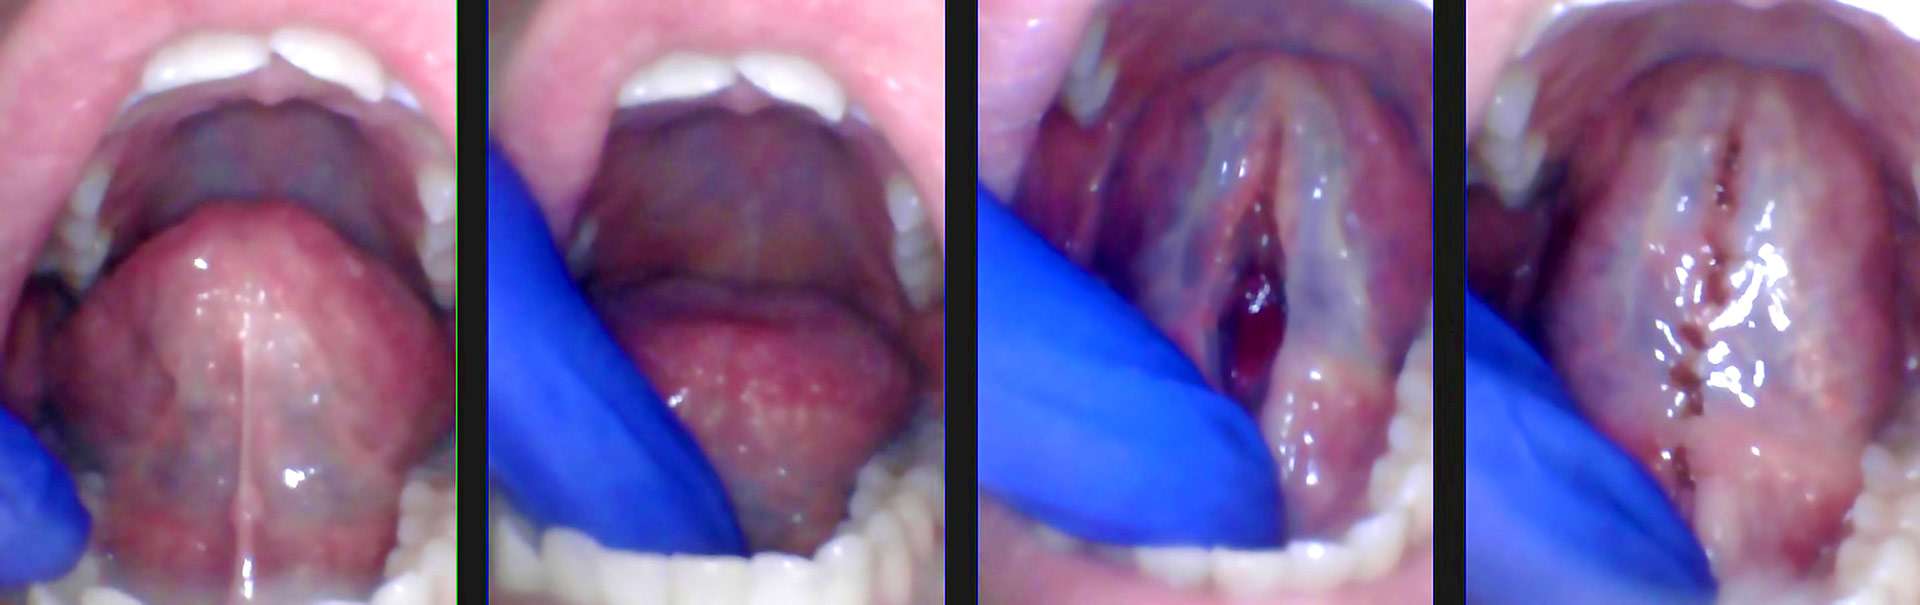

Most medical providers will ask a patient to stick their tongue out to check the tonsils, and many also think that protrusion is a good test for tongue mobility. However, sticking the tongue out is the least specific test for tongue mobility. That’s one reason so many patients go undiagnosed. A better test is to check the elevation of the tongue. Ask the patient to open wide (without pain or discomfort) and lift their tongue to the incisive papilla behind the maxillary incisors. If they can lift less than halfway, they are significantly restricted. Some patients will “cheat” and not fully open their mouth when lifting, or without realizing it, the floor of the mouth will lift up to try to get the tongue higher. You can use a gloved finger to hold the floor of the mouth down when they lift to get an accurate picture of their true mobility. The functional grading system by Zaghi and Yoon says that if the patient lifts less than 25% of the way, it’s a grade 4 tongue restriction. Between 25%-50% is grade 3, 50-80% is grade 2, and over 80% is grade 1.[4] To assess babies or children who are pre-cooperative, we use the knee-to-knee position and come from behind the head. Then use two fingers to lift under the tongue and isolate the frenum. This test is also useful during exams on adults to assess mobility during a hygiene check. You should check for a tongue restriction and assess mobility just like we screen for oral cancer. Oral cancer affects 1 in 10,000 adults.[5] While obviously a very different diagnosis, tongue-tie affects an estimated 1 in 4 patients of all ages and can cause life-altering symptoms.[2,3]

How do we treat a tongue restriction? We always work with a team approach, so we want a baby working with a lactation consultant, a child working with a speech or feeding therapist, and an adult working with a myofunctional therapist before the release. Additional bodywork, therapists, and medical providers are also needed depending on the symptoms and complexity. Otherwise, it would be like having knee surgery but no physical therapy. Your outcome will be suboptimal. After taking a comprehensive history, a full assessment (coming from behind the patient), and checking tongue mobility, we discuss these findings with the parents. A proper release would involve releasing the mucosa and fascia (connective tissue) above the genioglossus muscle. We always stay midline to avoid the lingual nerve or deep lingual vein. The genioglossus muscle limits the depth of the release. A diamond-shaped window under the tongue is opened using various methods, including scissors, scalpel, electrosurge, diode laser, erbium laser, or CO2 laser.